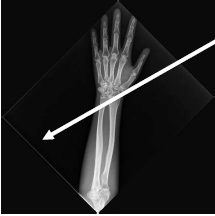

Analise a imagem a seguir:

Em relação à posição do antebraço mostrada na imagem, assinale a afirmativa correta.

Observe a imagem a seguir:

Trata-se de uma radiografia do antebraço esquerdo. O osso à direita se chama